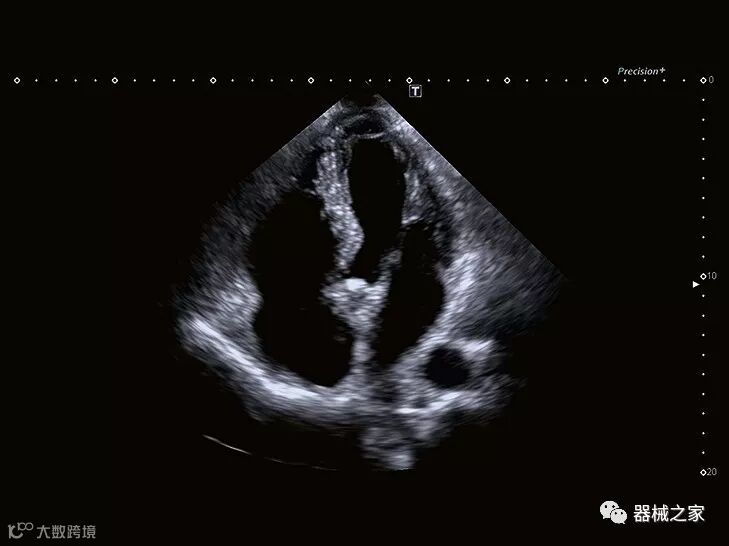

供应商已经超越了基本的二维和三维成像,提供了重建图像的新方法,以加快评估速度并使其更易于理解。

在RSNA 2018上发布的新成像被开发用于解决胎儿心脏和脑部成像问题。由于体积小且心率极快,因此难以进行详细的胎儿心脏评估。在18周时,胎儿的心脏大小与橄榄相当,每分钟跳动约150次。此外,结构本身非常复杂,婴儿不断运动,它始终是一个移动的目标。成像很重要,因为先天性心脏缺陷会影响全球每110个婴儿中的一个。

GE Healthcare用于胎儿超声的胎儿心脏和血管分析软件,在Voluson E10上提供,有助于在不到三分钟的时间内评估胎儿的心脏形状,大小和收缩性。称为辐射流的功能以三维视图显示血流。它还可以帮助显示缓慢流动的血液,例如神经血管循环。

在几年前,超声波无法对小型慢流血管中的血流进行成像,但现在有少数供应商提供具有此功能的系统。该特征提供了另外一种检查病变以指示癌症或炎症的方法。其中一个是佳能Aplio 900 CV系统,它可以显示毛细血管中的血流量。日立的Arietta 65中程系统提供了一种可视化小血管的功能,可以更好地观察肾脏等器官的灌注情况。三星RS85还提供MV-Flow可视化慢流微血管结构。

佳能Aplio 900 CV系统还在2018年推出了一种新方法,通过称为四腔室跟踪的回声可视化心脏。它在一个三维视图中跟踪所有四个腔室的血容量。它提供腔室的舒张末期和收缩末期视图。这允许一次完成整个心脏功能的图像,而不是一次查看一个腔室。

Baptist Health South Florida成为去年秋天西门子医疗保健公司Acuson Sequoia的首个商业安装网站。该系统将有助于增强胃肠病学,初级保健和减肥专业的成像能力。Sequoia可实现高分辨率成像,自动适应患者的体型和个人身体特征,有助于更加自信的诊断。它适应患者的组织密度,刚度和超声波束吸收的生物声学变化。这使得系统可以穿透高达40厘米而不会因衰减回波信号而导致图像质量下降。